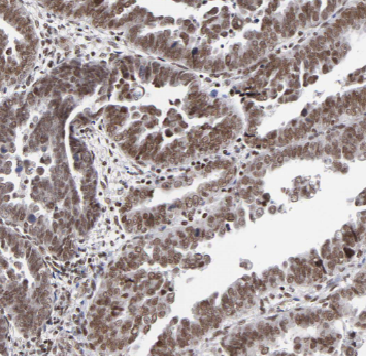

Immunohistochemistry of paraffin-embedded human ovary tumor tissue slide using FNab00494(APOBEC3C Antibody) at dilution of 1:200 heat mediated antigen retrieved with Tris-EDTA buffer(pH9).